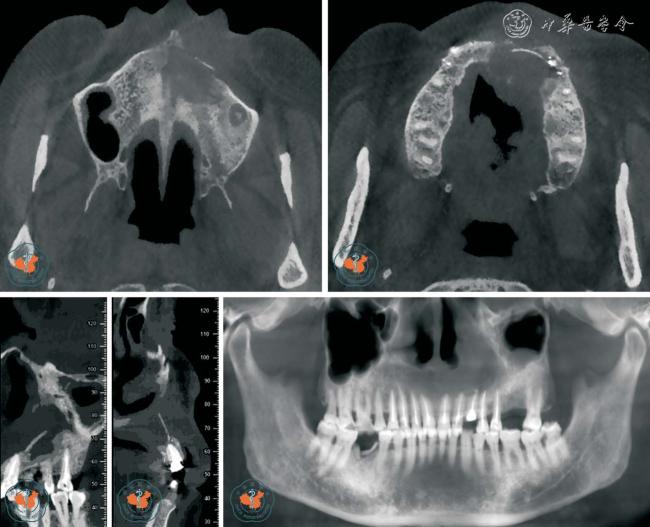

1. 正确判断根管数目: 根管数目的正确判断是根管治疗成功的主要因素之一。 Baratto Filho 等11采用体外研究、临床研究和CBCT 三种方法分析了上颌第一磨牙的根管解剖。 体外研究表明,140 颗离体牙中67.12%存在第四根管,其中1 例有7 个根管,存在第四根管的磨牙中92.58%第四根管位于近中颊根。 临床研究表明,53.26%及0.35%的磨牙分别存在4、5、6 个根管, 并且95.63%发生于近中颊根。 CBCT 研究表明,1.85%、37.05%、1.85%的磨牙分别存在2、4、5 个根管。 同时CBCT 对变异根管的发现和定位具有重要意义。 临床医师在根管治疗术前及术中可随时调用和调整CBCT 局部三维重建图像,从不同角度及层面观察根管的融合和分支情况,了解根管的形态、数目、走向、根尖处根管的位置是否融合等,是指导复杂根管系统牙齿治疗时的重要影像手段(图1 ~2)。

图1 CBCT 轴位显示左上颌第一磨牙5 个根管,其中侧支根管未根冲

图2 CBCT 轴位、VR 及MPR 重建冠、矢状位图像显示上颌中切牙变异根管